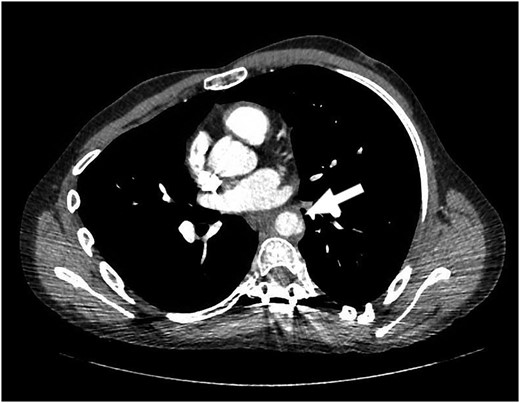

Our patient is a 24-year-old male with the EDS type VI who had undergone rod fixation of his spine for scoliosis, ocular surgery for a ruptured globe and ligation of his popliteal artery after an attempt was made to repair his aneurysm. The patient was being followed at Duke EDS Clinic where he underwent an extensive workup, and a definitive diagnosis was established. He presented to the emergency room (ER) after being kicked in the abdomen during a martial arts class. The patient felt an instant abdominal pain which resolved quickly. The patient went home after the incident and then developed nausea, vomiting and diaphoresis. He was hemodynamically normal in the ER. His groin pulses were slightly diminished compared with his radial pulses. The patient underwent a computed tomography (CT) scan of the chest, abdomen and pelvis with intravenous contrast. The patient was found to have traumatic aortic injury (Fig. 1). Cardiovascular surgery was consulted. The patient was admitted to the ICU for nonoperative therapy. He was started on Esmolol intravenously, and Diltiazem was added in order to keep his mean arterial pressure around 60. After 2 days in the ICU, the patient was transitioned to medications by mouth. He was allowed to ambulate on the fourth day and discharged on the eighth day after a long discussion with him and his family.

The patient returned to the hospital less than a week later in extremis. He had severe back pain and was diaphoretic. The patient was hypotensive and tachycardiac. He had no femoral pulses. Repeat CT scan revealed extension of the aortic injury in the abdominal aorta with no flow in the iliac (Figs 2–4). The patient was emergently taken to the operating room (OR) where the aorta, iliac and femoral vessels were unable to hold sutures. We were unable to repair this patient's aorta. Post-operatively, we spoke with the family, and the patient was allowed to expire.

Note contrast in the distal aorta but no contrast in the iliac arteries.